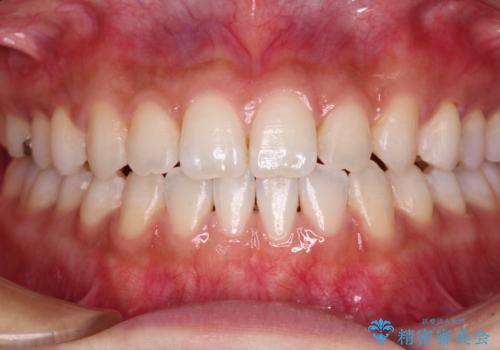

最終的には隙間は全て閉じ、綺麗な仕上がりとなりました。

一度インビザラインのマウスピースセットをお渡しすると1年以上来院されず、マウスピースを破損したり紛失したりすると来院されるというのんびりとしたペースで治療を行ったため、4年間という長期にわたる治療となりました。

- 上顎前歯の隙間を気にして来院された患者様です。

目立たない装置を希望とのことで、インビザラインを用いて矯正治療を行うこととしました。